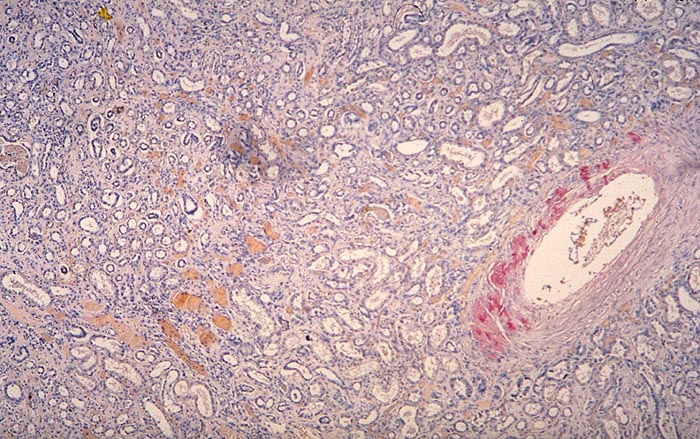

Diagnose

Amyloidose der Gefässe

Beschreibung

Ausschliesslich Amyloidablagerungen in einer Arterienwand.

Zusatzbefund

Glomeruli und Interstitium negativ. AL-Amyloid.